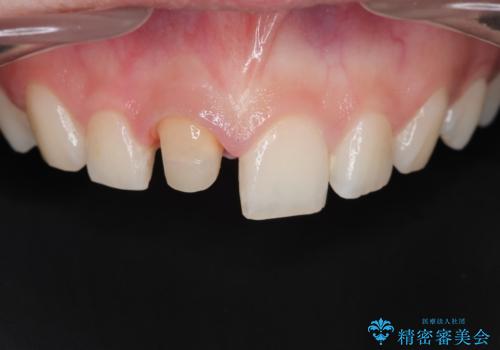

前歯が欠けた。

- 前歯が欠けたとの事で来院。

セラミックを希望されたので根管治療からやり直しました。